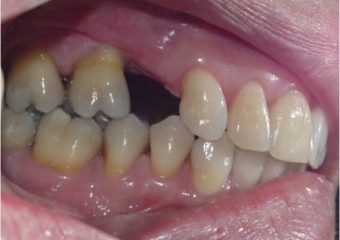

Imagem final da prótese fixa em porcelana sobre implante, caso finalizado em Dezembro de 2011